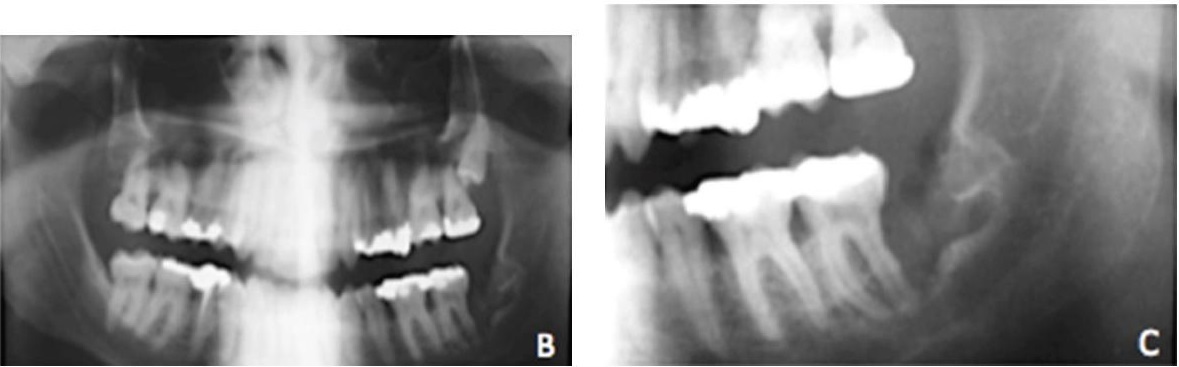

Киста на корне зуба: фото до и после